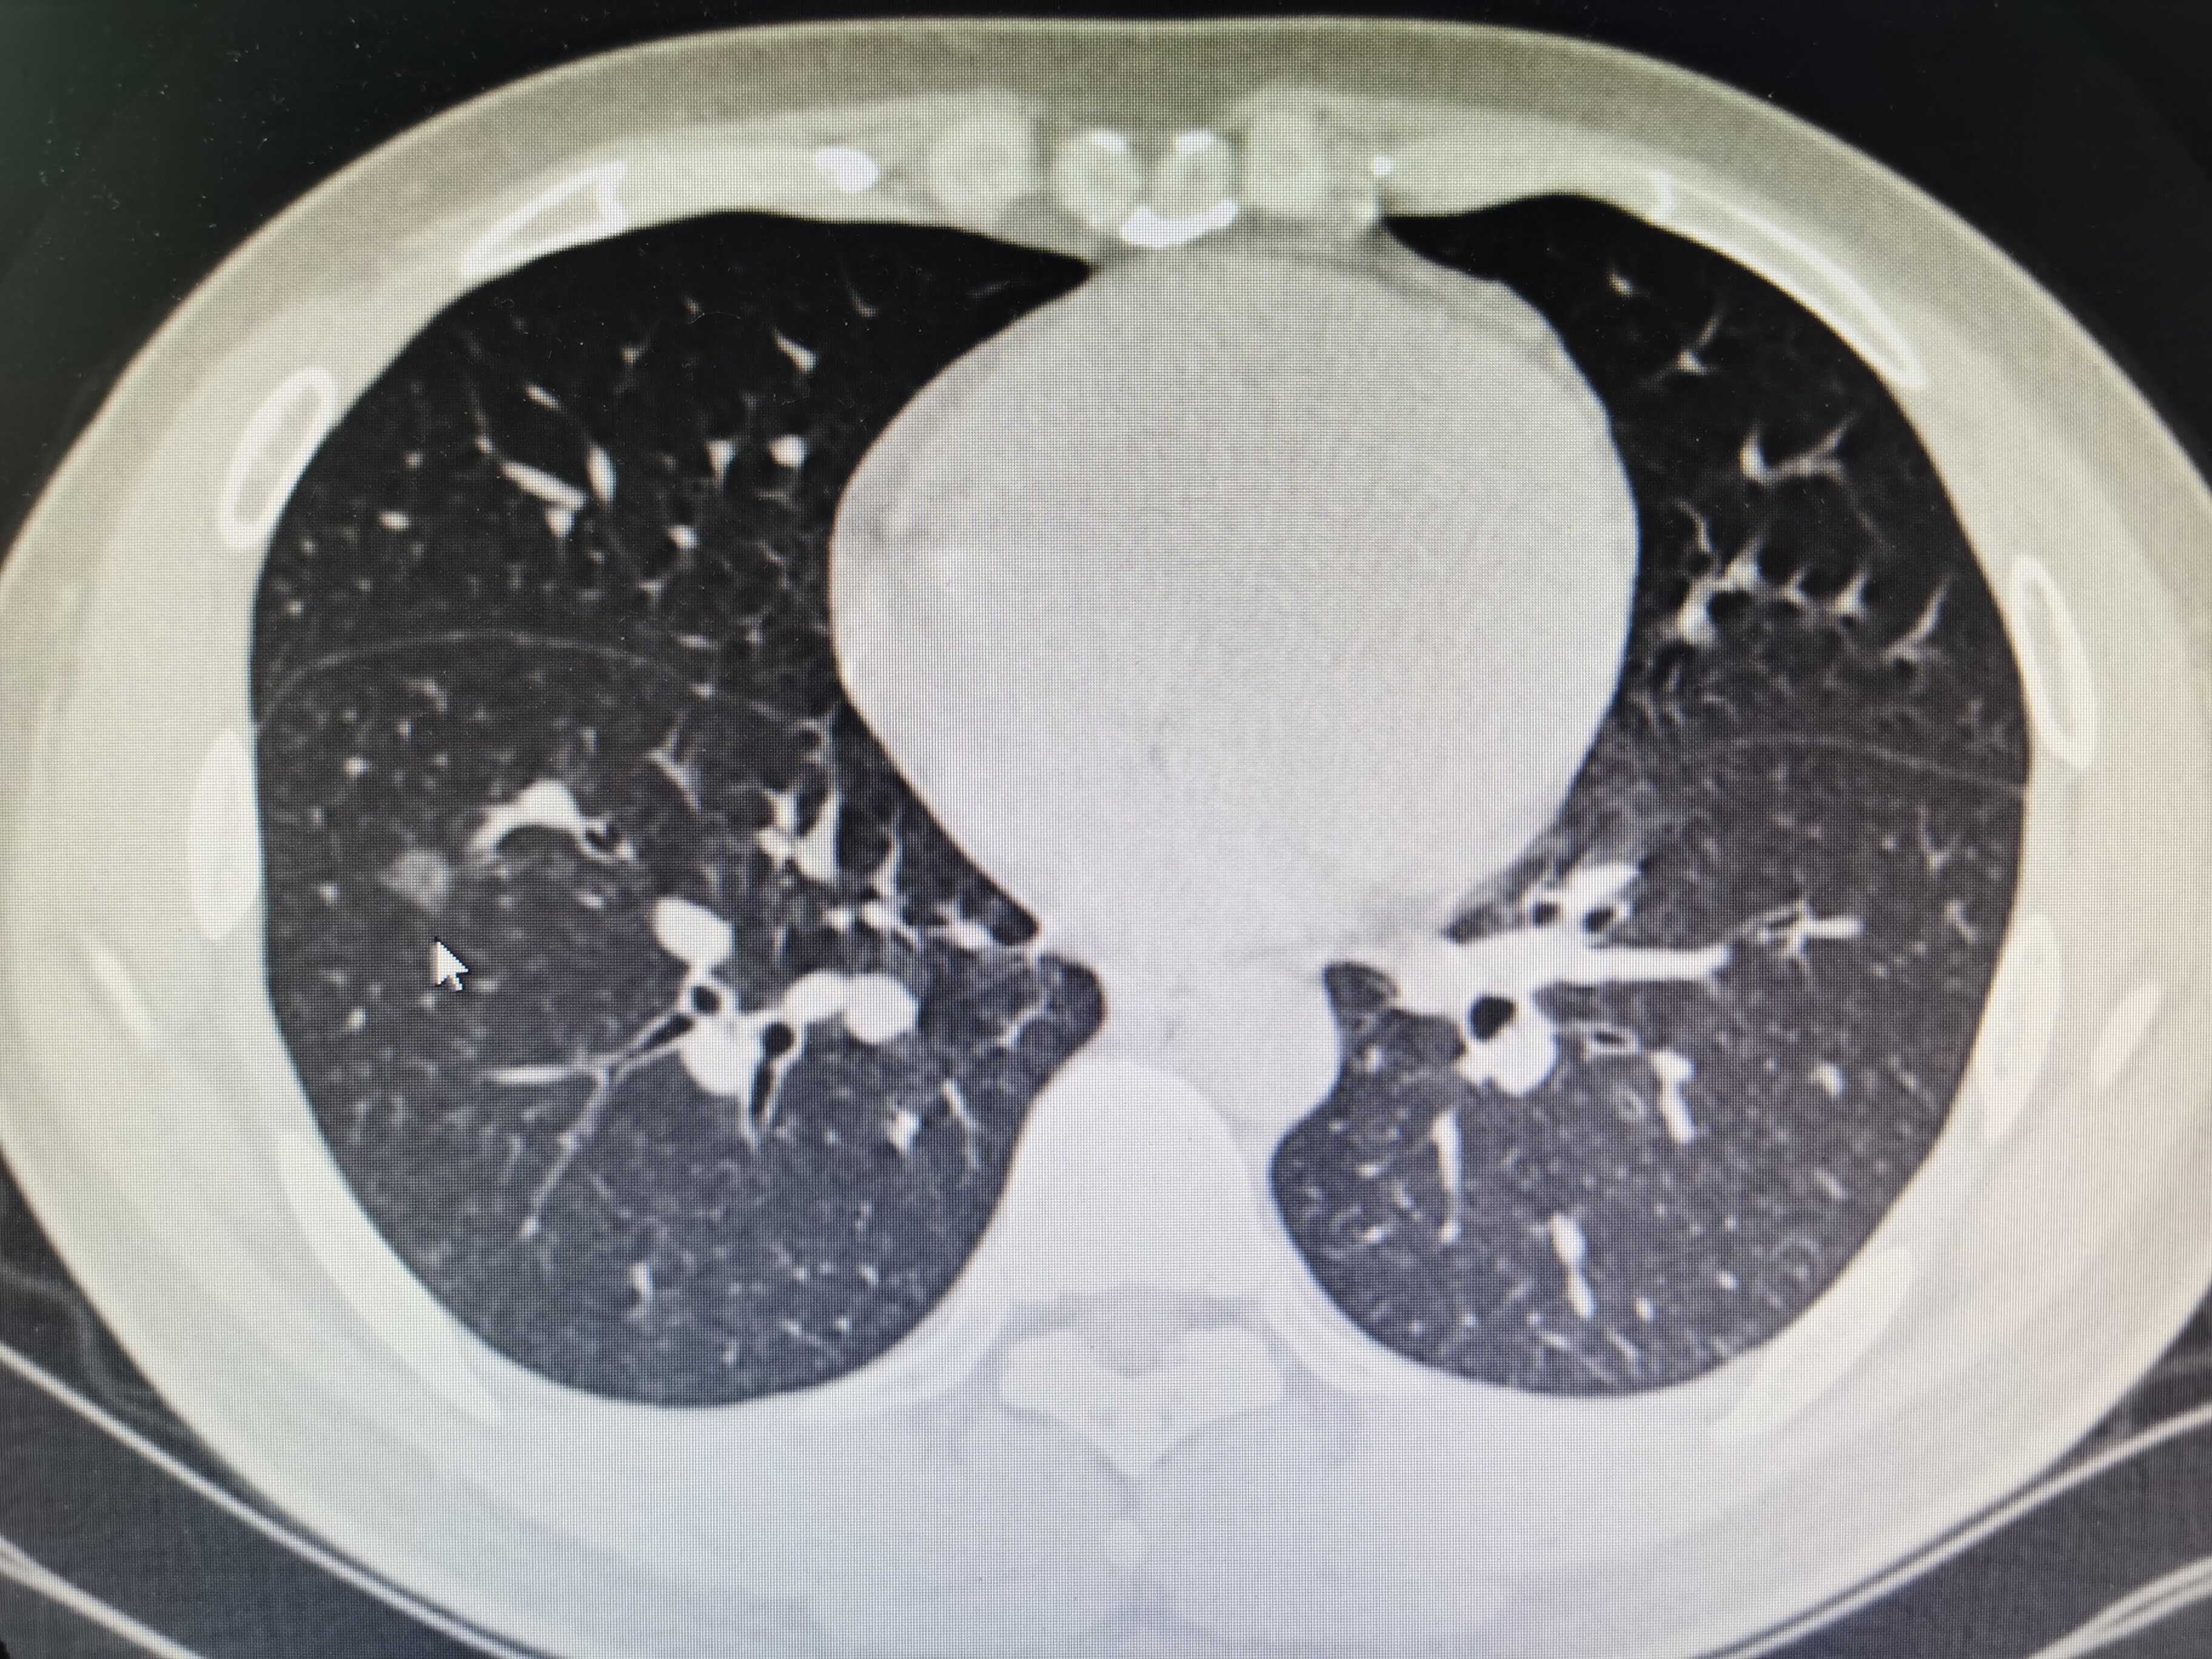

肺部结节是肺部影像学发现的和正常肺里结构不太一样的情况,肺部影像学即为胸片或者是肺部的CT,通过这种检查可以看到肺的细微结构。

肺结节在临床上一般是按大小区分的,小于3cm的,一般称为肺结节,大于3cm的称之为肿块。

肺结节的再具体细分的话,还可以分为小于1cm的肺微小结节,1-2cm之间是为肺小结节,2-3cm之间的称为肺结节,肺结节有单发的也有多发的,单发的有良性和恶性之分,良性的主要常见于肉芽肿、错构瘤或者肿大的淋巴结或者炭末沉积。